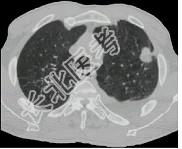

- 单项选择题女,64岁, 胸背疼痛1周,CT检查如图, 最可能的诊断为 ( )

A、左上肺结核球

B、左上肺周围型肺癌

C、左上肺炎性假瘤

D、左上肺单发性转移癌

E、左上肺错构瘤